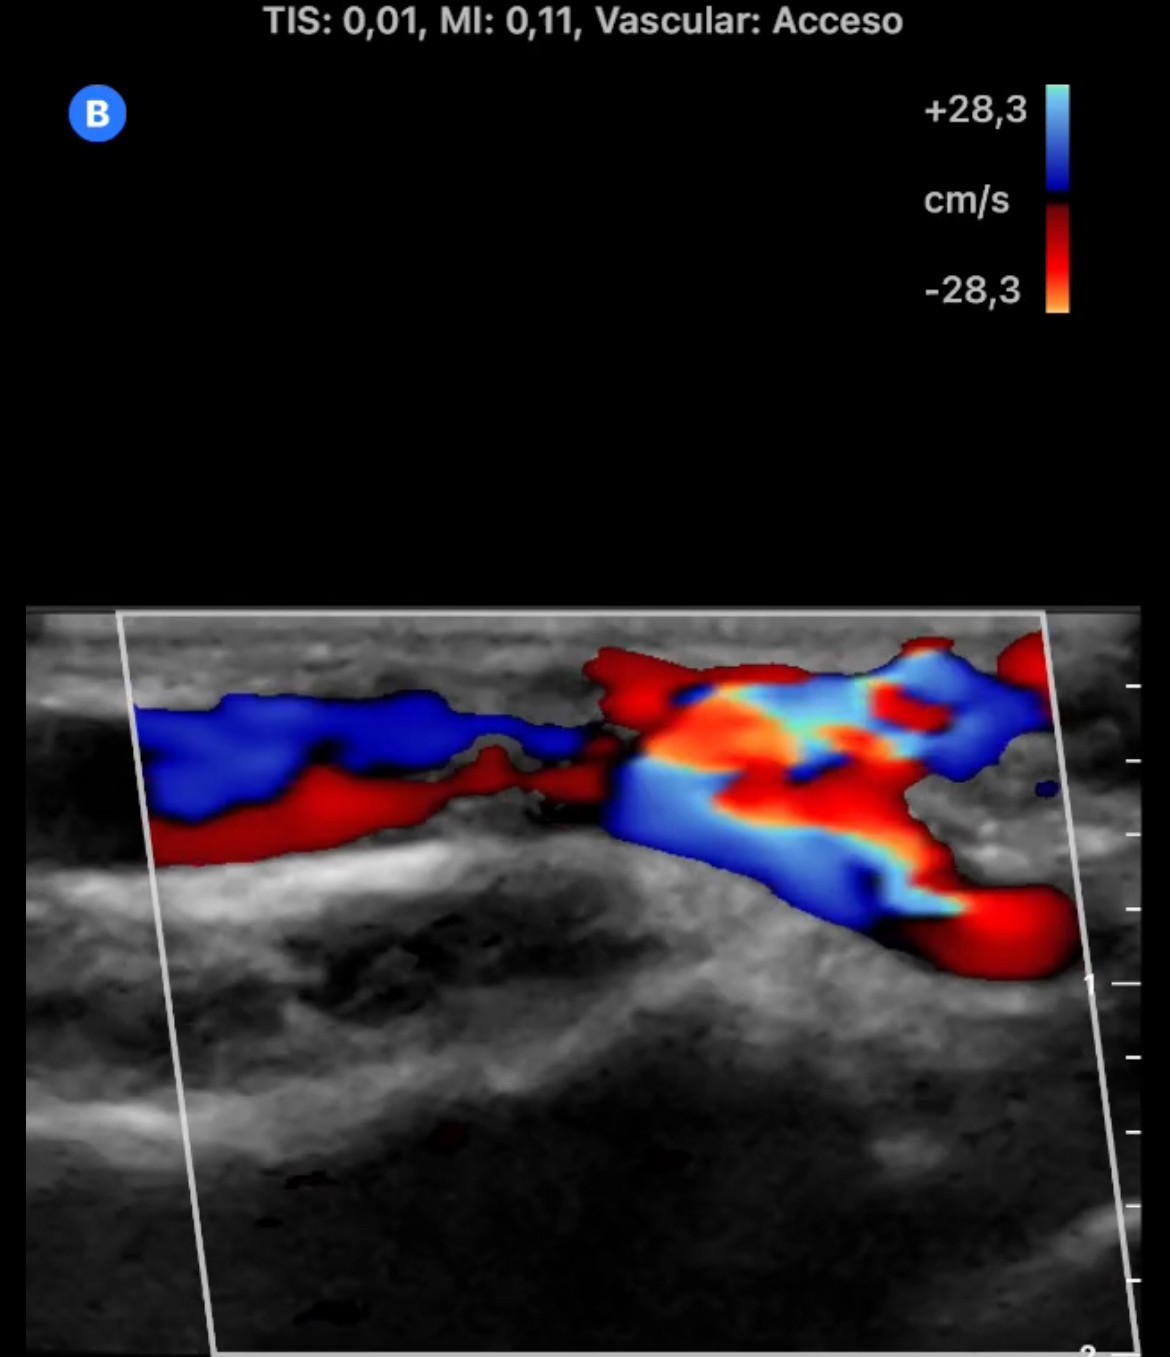

En la cara palmar de la muñeca derecha se aprecia un aumento de tamaño de las venas superficiales con flujo Doppler color en su interior. En arteria radial se observa flujo muy turbulento con comunicación de arteria radial con una vena superficial del antebrazo.